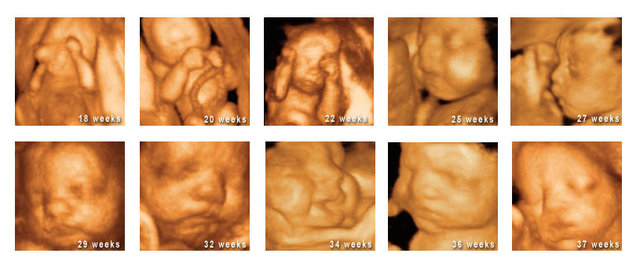

• fetal growth

fetal growth

this stage is marked by amazing change and growth. during the third month gestation, the sex organs began to differentaite and by the end of the month all the parts of the body will be formed, at this point the baby weighs about three ounces, this domain is physical..

• heartbeat

heartbeat

During this time the heartbeat grows stronger and other body systems become further developed. The fingernails, hair, eyelashes and toenails form and most noticeably. this domain is physical

• size

size

By now the fetus has increased dramatically in size, about six times in size. The brain and central nervous system also become responsive during this time. this domain is physical

• mature

mature

The brain starts to mature much faster with the activity that greatly resembles a sleeping newborn. The fetus continues to develop, put on weight, and prepare for life outside of the womb. The lungs begin to expand and contract, preparing the muscles for breathing. this domain is physical